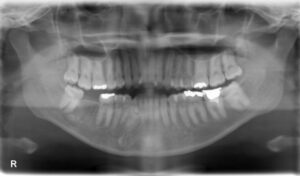

下顎大臼歯1本欠損症例

BEFORE AFTER 48歳男性/下1本欠損/インプラント埋込手術 【治療内容】 右下第二大臼歯の虫歯が大きく進行し…